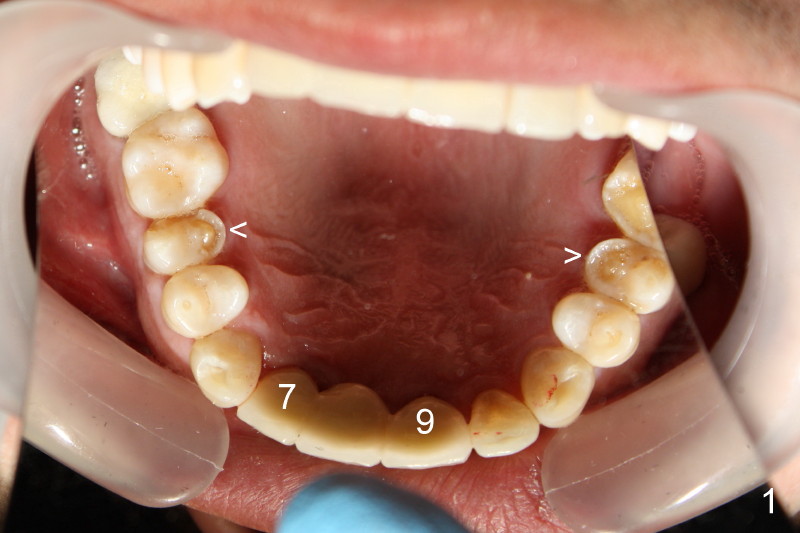

Fig.1 was taken when the new bridge was temporarily cemented (mirror view, Jan. 28, 2010). Arrowheads indicate enamel chip from the lingual cusps of the upper 2nd premolars. On Nov. 11, 2010, the bridge became loose again and was cemented permanently. Two months later (Jan. 27, 2011), porcelain chipped again as shown in Fig.2 and 3 (white arrowheads; black arrowhead points to wear facet of the tooth #6). The chipped bridge was removed.

This time PFM FPD was fabricated with lingual metal as shown in Fig.4. The bridge was temporarily cemented on Feb. 09, 2011. Night guard was fabricated later. Unfortunately the bridge came off 7 months later and was recemented temporarily. Permanent cementation was not attempted, because of potential porcelain chip or implant/abutment screw loosening due to bruxism. Yesterday, the patient reported that the bridge was loose again. Today, #7 build-up changed from loose, disintegrated Cavit to more solid composite (Fig. 5 to 6). The bridge was cemented temporarily to avoid porcelain chip related to permanent rigid cementation. Fig.7 shows occlusal equilibrium after cementation. The patient felt that there was no premature contact to the bridge. What should we do next? Can we add an implant at the site of #8. Can this alleviate bruxism-related problems (easy decementation, porcelain chip and possible loosening of screw between abutment and implant)? Thanks.